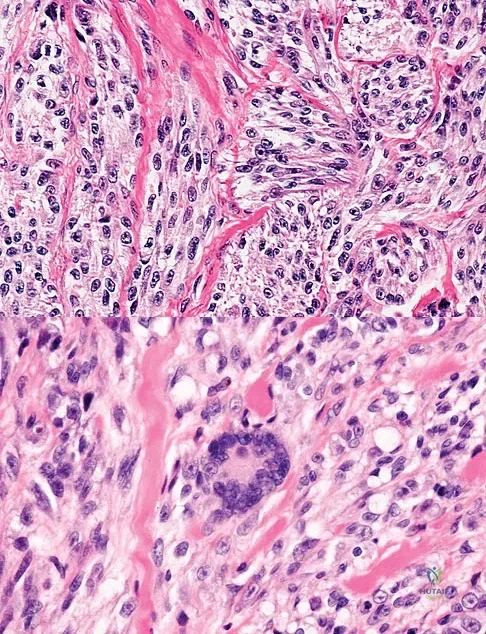

A 35-year-old man reports the development of a painful 2-cm nodule on his dorsal wrist over the past 3 years. A surgeon excised the lesion with a presumptive diagnosis of a ganglion cyst. Histology sections from the excision are shown in Figures 11a and 11b. What is the most likely diagnosis?

Explanation